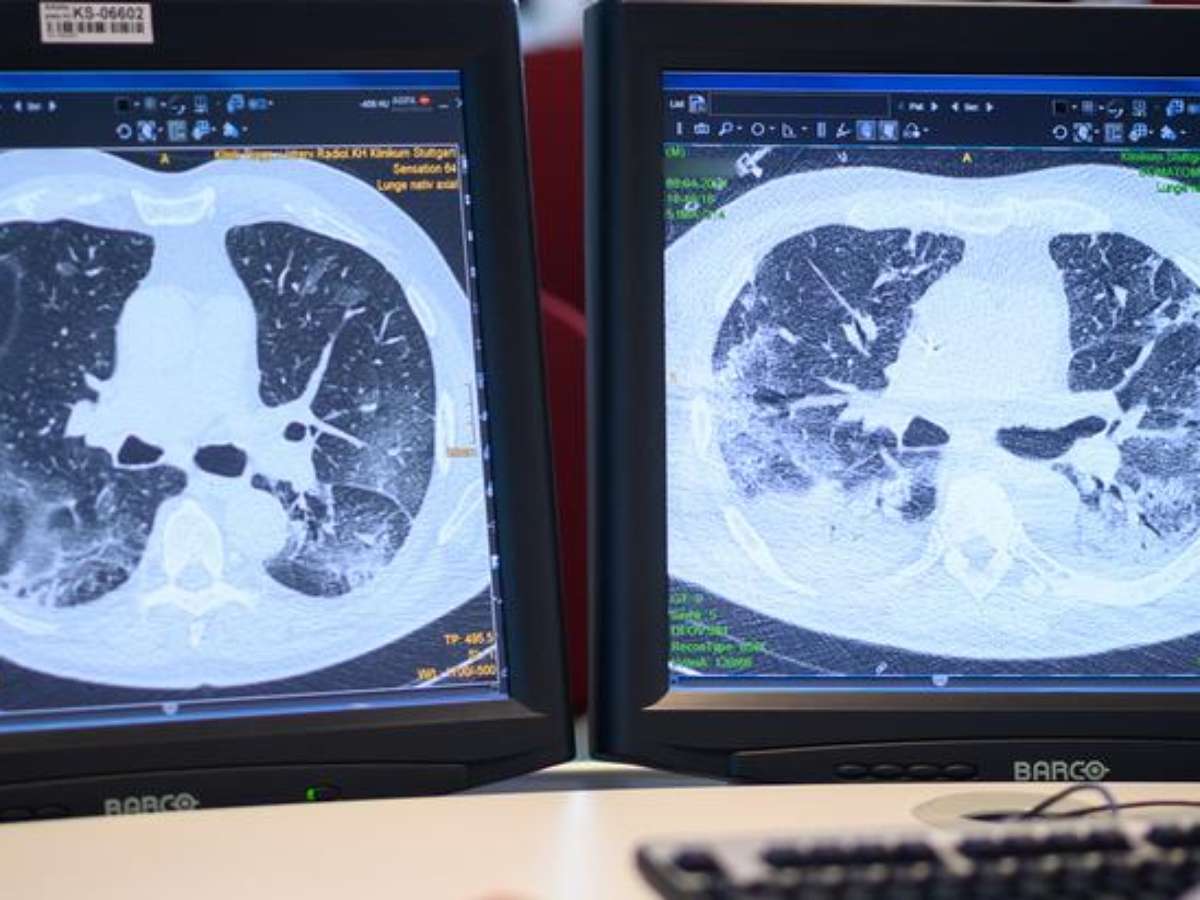

Muitos pacientes apresentam como sequela uma redução da capacidade pulmonar

No decorrer da covid-19, os pulmões são fortemente atacados, mas o dano nem sempre para por aí: muitos pacientes apresentam como sequela uma redução da capacidade pulmonar. Cientistas chineses detectaram um turvamento semelhante a vidro leitoso nas tomografias de doentes recuperados, sugerindo a ocorrência de lesões permanentes.

Pesquisa-se no momento se esses pacientes desenvolveram fibrose pulmonar, uma formação patológica de tecido cicatricial. Ao enrijecer o tecido dos pulmões, ela pode dificultar o transporte de oxigênio para os vasos sanguíneos, provocando em respiração superficial e rápida, e tosse seca e irritável. O resultado é uma queda do desempenho físico, tornando difíceis até mesmo atividades quotidianas.

A fibrose pulmonar é irreversível, já que as cicatrizes no órgão não retrocedem, porém seu progresso pode ser desacelerado ou mesmo sustado, se ela é detectada a tempo.